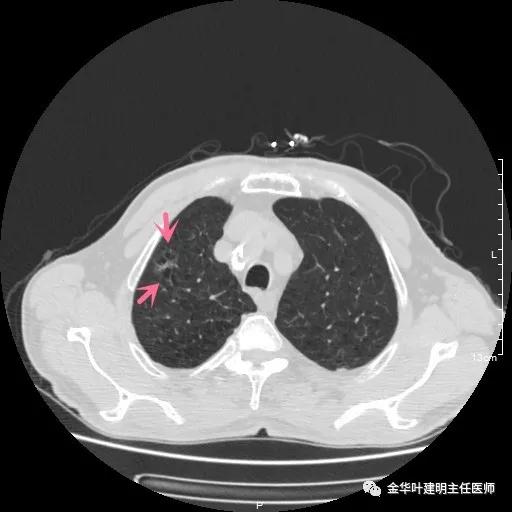

以上示右中叶病灶4。也是囊腔型病灶,病灶大,囊壁是磨玻璃密度,亦是较为典型的囊腔型肺癌影像。单病灶看,需中叶切除来治疗,因病灶3的存在,中叶切除可同时解决病灶3与病灶4。